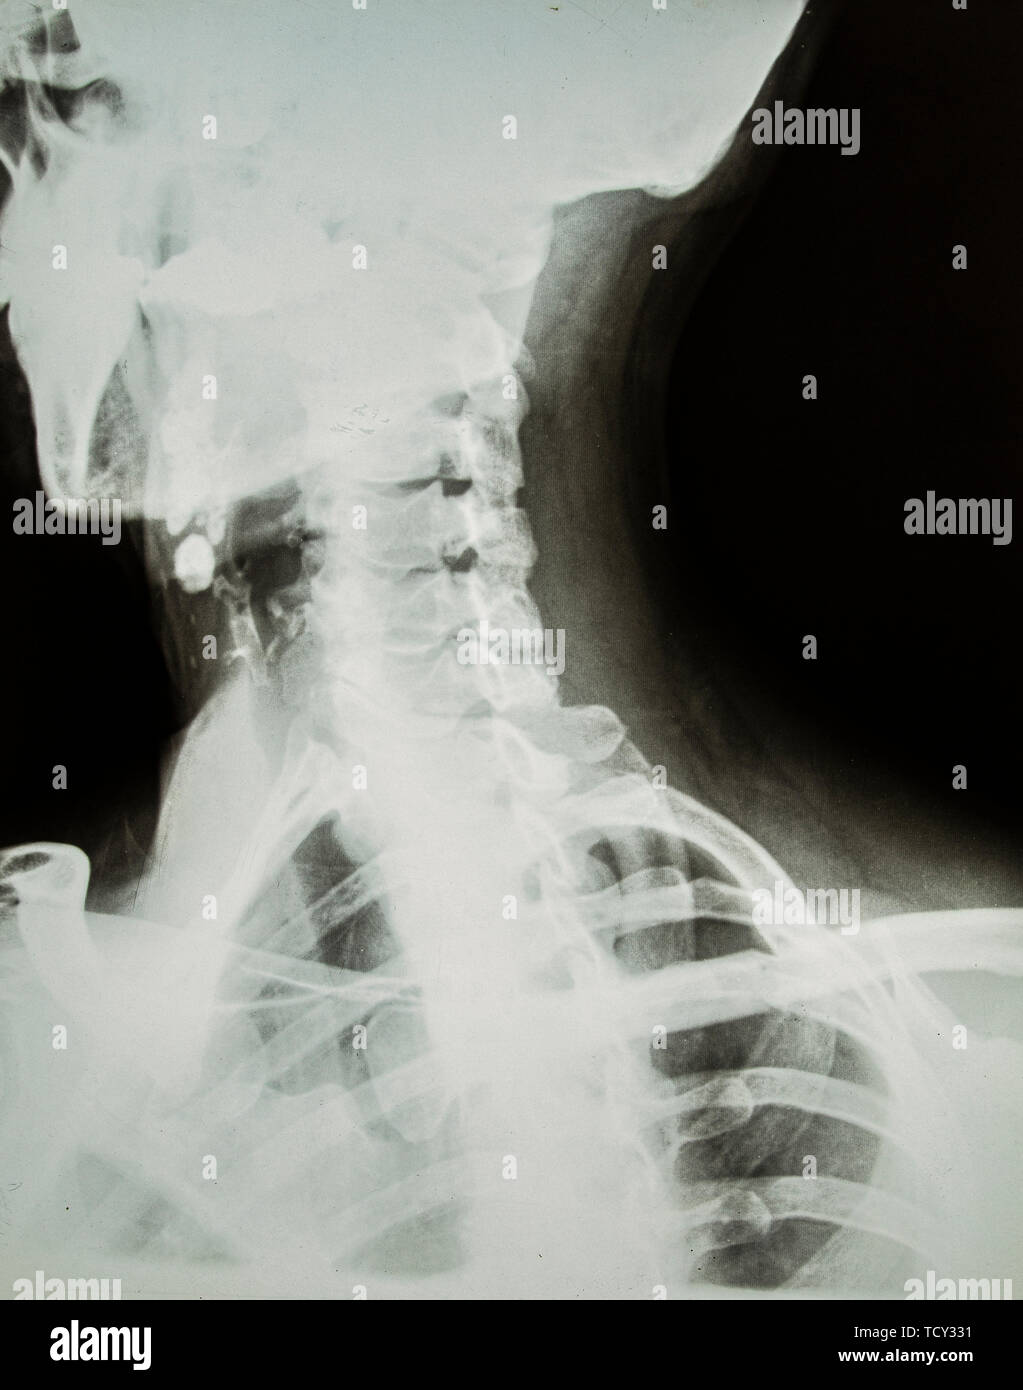

From www.alamy.com

Neck face anatomy hires stock photography and images Alamy Head And Neck X Ray Anatomy in the neck we can distinguish the oral cavity, the pharynx (divided in rhinopharynx, oropharynx, and. In addition, we’ll also cover the most important blood vessels and nerves supplying each region. applying our head and neck anatomy knowledge, we’d expect to see these vessels of the carotid sheath located laterally to the lobes of. Strictures, acute syndromes, neoplasms. Head And Neck X Ray Anatomy.